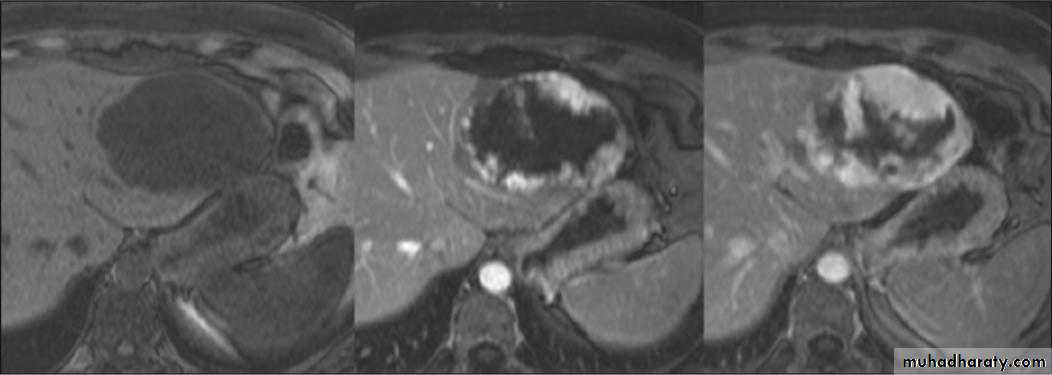

Hemangioma